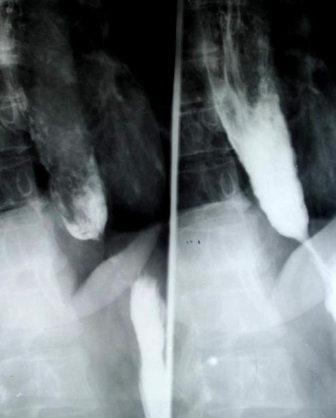

Neoplasm esofagian malign vegetant